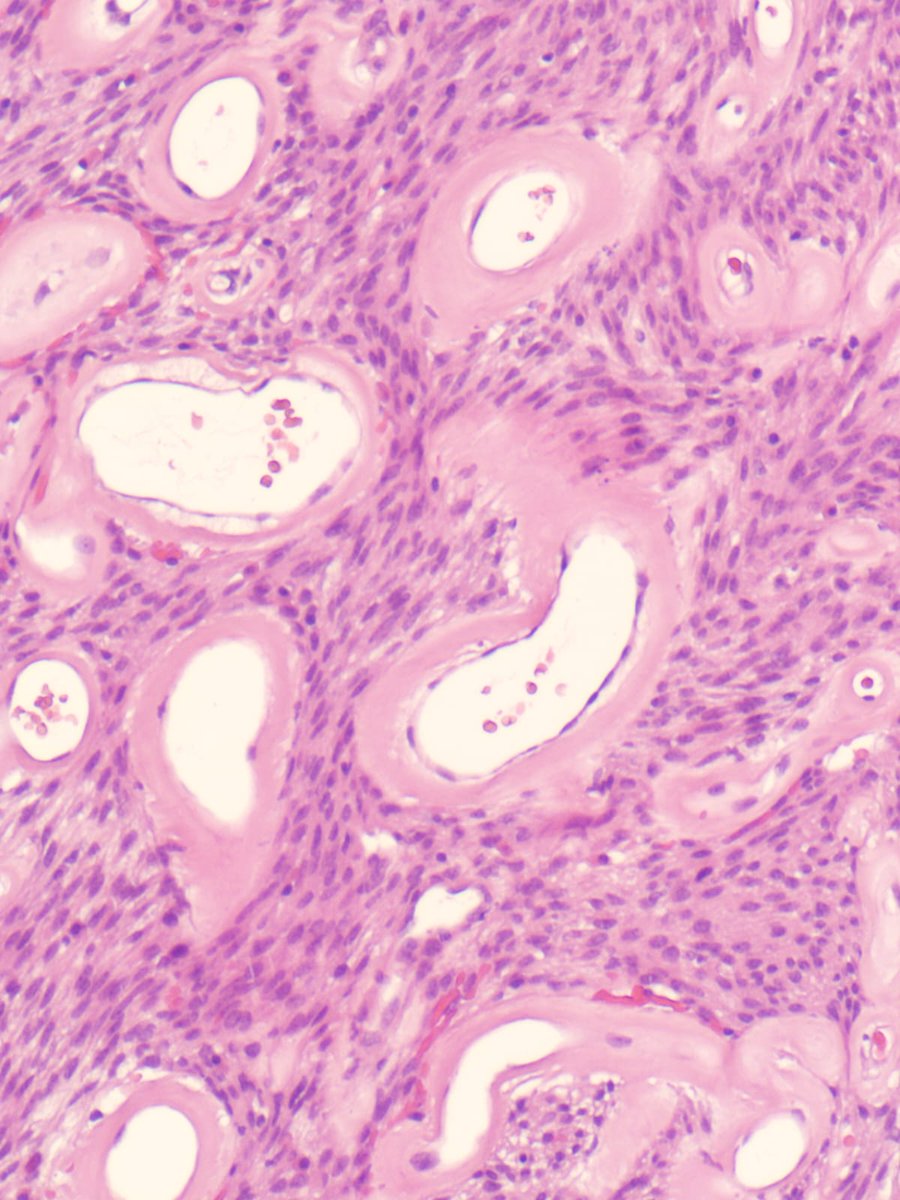

52F with a right-sided mass near the TMJ. How would you interpret the FNA? A) Non-Diagnostic B) Neoplasm - Benign C) Neoplasm - SUMP D) Malignant #CytoPath #GUPath #PathTwitter #pathology

52F with a right-sided mass near the TMJ.

How would you interpret the FNA?

A) Non-Diagnostic

B) Neoplasm - Benign

C) Neoplasm - SUMP

D) Malignant

#CytoPath #GUPath #PathTwitter #pathology